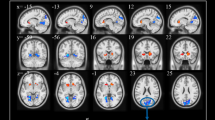

To investigate the relationship between the ReHo values and PANSS scores in FES, we performed the voxel-wise correlation analyses between the ReHo map and PANSS scores, using age, gender, education, and illness duration as covariates. There was a significant negative correlation between the PANSS total score (r = −0.40, p < 0.05, corrected by TFCE; Fig. 2a) and the ReHo value in the right precentral gyrus, and a significant positive correlation between the PANSS total score (r = 0.49, p < 0.05, corrected by TFCE; Fig. 2b) and the ReHo value in the left thalamus. Significantly positive correlation between the positive factor (r = 0.45, p < 0.05, corrected by TFCE; Fig. 2c) and ReHo value was observed in the right Thalamus. Moreover, we also found the disorganized/concrete factor (r = 0.38, p < 0.05, corrected by TFCE; Fig. 2d) was significantly positively correlated with ReHo value in the left posterior cingulate gyrus (PCG). There was a significant positive correlation between the excited factor (r = 0.44, p < 0.05, corrected by TFCE; Fig. 2e) and the ReHo value in the left precuneus. In addition, the depressed factor was significantly negative with ReHo value in the right postcentral gyrus (r = −0.38, p < 0.05, corrected by TFCE; Fig. 2f), and was significantly positive with ReHo value in the right thalamus (r = 0.50, p < 0.05, corrected by TFCE; Fig. 2g). The results of these voxel-wise correlation analyses are shown in Table 4.

The correlation analysis showed the PANSS total score negatively correlated with ReHo in the right precentral gyrus (a) and positively correlated with ReHo in the left thalamus (b), the positive factor positively correlated with ReHo in the right thalamus (c), the disorganized/concrete factor positively correlated with ReHo in left PCG (d), the excited factor positively correlated with ReHo in the left precuneus (e), and the depressed factor negatively correlated with ReHo in the right postcentral gyrus (f) and positively correlated with ReHo in the right thalamus (g). Significant correlations between PANSS and ReHo were defined as p < 0.05, TFCE corrected after correcting for age, gender, education, and illness duration. Warm and cool color indicate positive and negative correlation, respectively